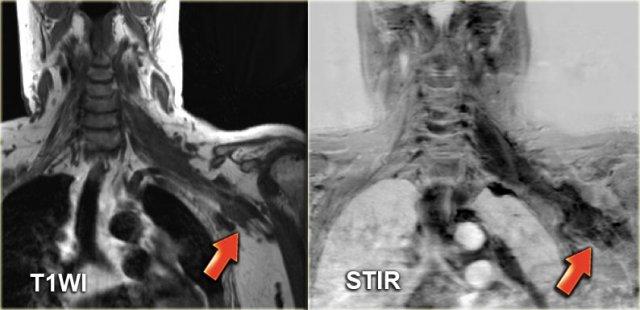

Bên trái là hình ảnh của một phụ nữ 67 tuổi có tiền sử u lympho không Hodgkin.

Bệnh nhân gần đây phát hiện sưng nề ở bên trái cổ.

Bước 1

Hình ảnh CT tại mức dây thanh âm thật cho thấy một khối rõ ràng nằm trong khoang cổ sau.

Bước 2

Khối có bờ rõ và đồng tỷ trọng với cơ.

Hình ảnh tái tạo mặt phẳng coronal cho thấy khối có hình dạng thuôn dài, kéo dài về phía nách theo đường đi của đám rối thần kinh cổ-cánh tay.

Tiếp tục xem các hình ảnh MRI.

Tổn thương xuất phát từ lỗ liên hợp thần kinh bên trái và phát triển dọc theo đường đi của đám rối thần kinh cánh tay (mũi tên đỏ).

Thực chất, chúng ta đang quan sát thấy hình ảnh đám rối thần kinh bị dày lên rõ rệt.

Bước 3

Đặc điểm hình ảnh học xác nhận nguồn gốc thần kinh của khối.

Kết hợp với tiền sử bệnh, chẩn đoán cuối cùng là thâm nhiễm lan tỏa đám rối thần kinh cánh tay trái do u lympho không Hodgkin tái phát.